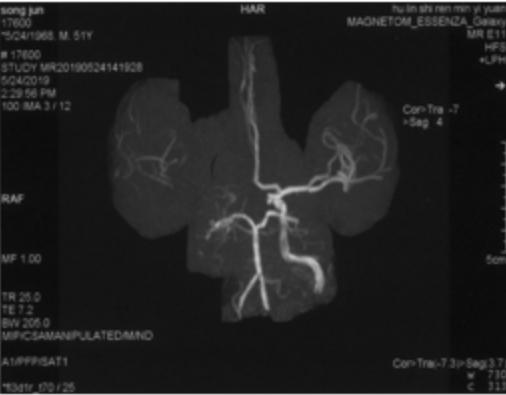

2019-07-20外院PWI:右侧额颞叶灌注信号减低(图4)。

图4